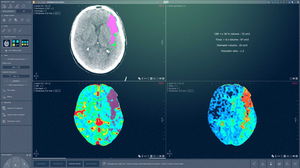

... Tome decisiones de tratamiento rápidas tras un examen neurológico en el contexto de una evaluación o sospecha de ictus. Acelere la toma de decisiones y mejore el tiempo de gestión del paciente. Simplifique su análisis con herramientas ...

Intrasense